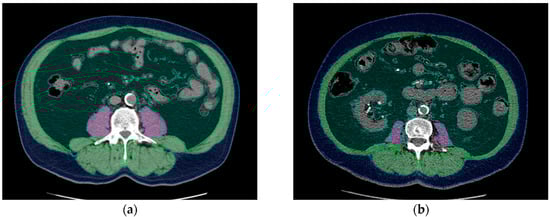

Cut-off values for sarcopenia significantly predicted uncensored 1-year uncensored kidney transplant survival (p = 0.05), and the values for obesity significantly predicted 3-year and 5-year uncensored kidney transplant survival. The results are compiled in Table 8.

The influence of sarcopenia on 1-year uncensored kidney transplant survival and the influence of obesity on 5-year uncensored kidney transplant survival are shown in Kaplan–Meier curves (Figure 2). The log-rank showed the significant influence of sarcopenia and obesity (p = 0.002 and p = 0.007, respectively).

Figure 2. (a) Graph showing that sarcopenia assessed by a routine pretransplant computed tomography (CT) scan may influence 1-year uncensored graft survival. Log rank test: p = 0.002. (b) Graph showing that obesity may influence 5-year uncensored graft survival. Log rank test: p = 0.007.